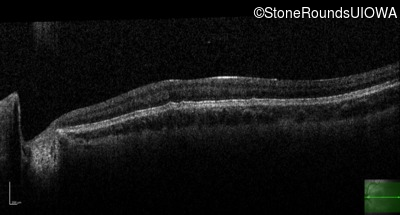

Optical Coherence Tomography - Left - 20/100

Exemplar / OCT Stack

OCT Stack